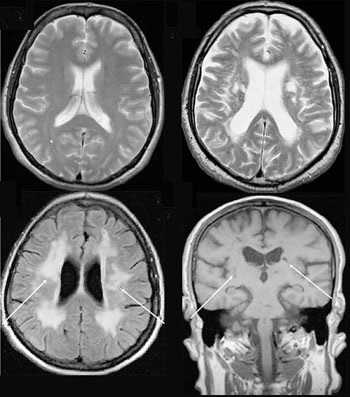

Магнитно-резонансная томография

В основе МРТ лежит явление магнитного резонанса, основанного на переизлучении радиоволн, взаимодействующих с атомами водорода, в избытке содержащимися в организме человека. Эти переизлученные электромагнитные волны улавливаются датчиком МР-томографа, усиливаются и в виде цифровых изображений появляются на экране монитора. Это безвредный и абсолютно безопасный для здоровья человека метод лучевой диагностики, так как в основе получения изображения отсутствует рентгеновское излучение, поэтому МРТ можно проходить неограниченное количество раз, с любым интервалом.

Существенное преимущество МР-томографии перед КТ заключается в том, что она не противопоказана беременным во II и III триместре и совершенно безопасна для детей. В МРТ исследуемая область сканируется в трех проекциях, что позволяет врачу-рентгенологу в полной мере оценить состояние тканей и органов исследуемой области, а высокая контрастность изображения и пространственное разрешение позволяют визуализировать серое и белое вещество головного мозга, оценивать состояние костного мозга и мягких тканей различной локализации. Кроме того, метод МРТ позволяет получать изображения сосудов головного мозга и сосудов шеи без введения контрастного препарата.

МРТ или магнитно-резонансная томография строит свою работу на принципе ядерного магнитного резонанса. Томограф работает с ядрами атомов водорода, которые есть в клетках тканей, имеющих воду составным элементом. Сначала аппарат МРТ создает сильное магнитное поле, а затем начинает на него воздействовать радиочастотным излучением. Протоны атомов водорода клеток пациента, находясь под таким воздействием, начинают колебаться и выстраиваются вдоль магнитного поля на очень короткий срок. Затем они возвращаются на исходные позиции, выбрасывая энергию. Именно ее улавливает компьютер МР-томографа и декодирует в трехмерные объемные, анатомически очень точные изображения.

Поскольку для хорошей визуализации магнитно-резонансному томографу нужно много клеток с атомами водорода, то ткани с большим содержанием воды лучше всего визуализируются на МРТ снимках. Поэтому МР-томография позвоночника очень хорошо показывает: